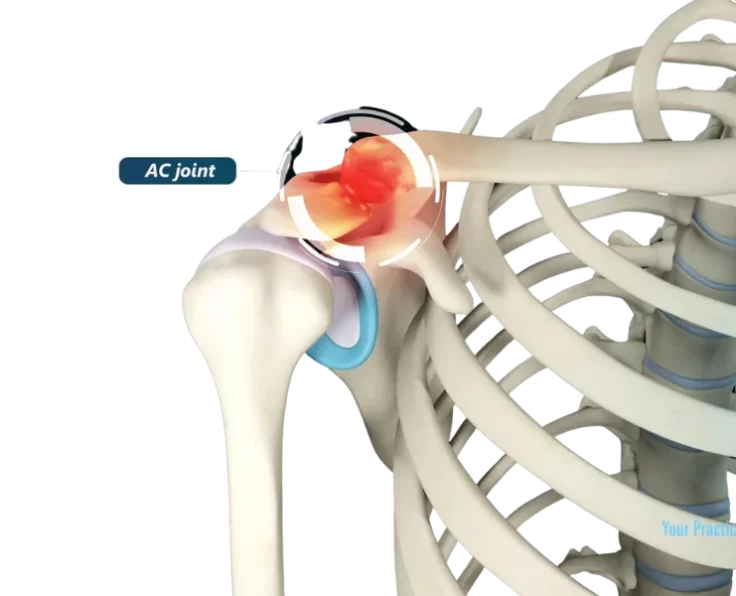

AC Joint Reconstruction

The acromioclavicular joint, often known as the AC joint, is positioned on the top of the shoulder, where the clavicle (collarbone) meets the acromion (shoulder…

AC Joint Excision

The goal of the procedure is to remove the uncomfortable and injured Acromioclavicular Joint (ACJ) without causing it to become unstable.